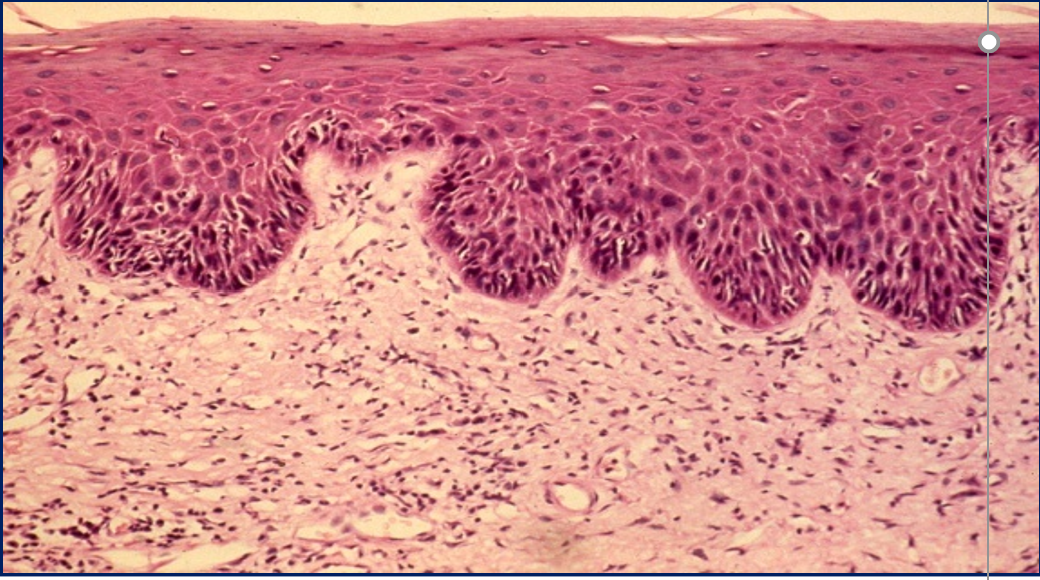

How to tell difference btw MM pemphigoid and Pemphigus Vulgaris on histological slide

A

MM Pemphigoid will be seen in linear spaces UNDER the basal cells

• Btw the basement membrane and epithelium

Dysplasia

• Tear shaped rete ridges

• Abnormally superficial mitosis

• Increased number of mitotic figures